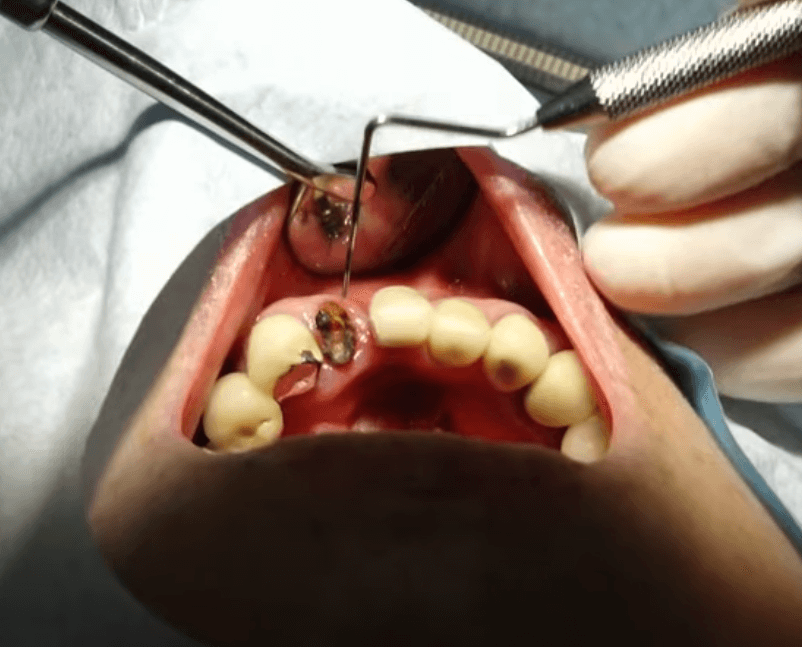

임플란트 주위염은 임플란트 수술 후 발생할 수 있는 주요 합병증 중 하나로, 특히 구강 위생이 소홀해지면 자주 나타날 수 있는 증상입니다. 이 질병은 주로 치주에 대한 관리가 부족할 경우 발생하며, 이로 인해 어렵게 심은 임플란트가 뽑히거나 탈락하는 등의 부작용을 유발할 수 있습니다. 임플란트 주위염은 일반적으로 치주염과 유사한 증세를 보이며 초기에는 발견이 어려울 수 있습니다. 이러한 이유로 정기적인 검진이 더욱 중요하며, 초기에 증상을 발견하여 조기에 대처하는 것이 필요합니다.

만약 임플란트가 흔들린다면, 이는 크게 두 가지 주된 원인으로 나뉩니다. 첫 번째로는 임플란트를 구성하는 나사가 헐거워져서 풀어지는 경우입니다. 이 경우에는 나사를 다시 적절히 조이면 문제를 해결할 수 있으며, 비교적 간단한 조치로 신속한 치료가 가능합니다. 그러나 두 번째로, 임플란트 주위염이 원인인 경우에는 상황이 다릅니다. 임플란트 주위염은 임플란트와 치조골 사이의 골 결합이 파괴될 때 발생하며, 이 경우에는 임플란트를 다시 수술하여 재픽싱하는 것이 필요할 수 있습니다. 이는 좀 더 복잡한 치료를 필요로 하며, 빠른 대응이 요구됩니다. 따라서 임플란트의 느슨함이 발견되면, 원인을 신속히 확인하여 적절한 치료 방법을 찾는 것이 중요합니다.